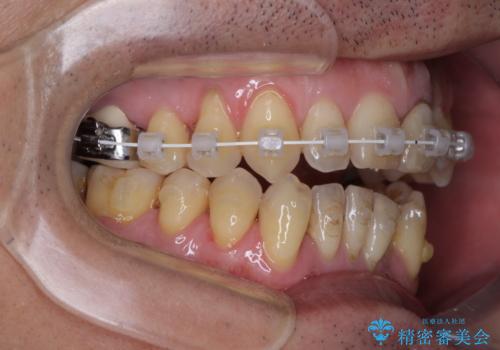

開咬の改善には、舌の突出癖改善のためにトレーニングを行いつつ、インビザラインでの矯正治療が大変有効ですが、上顎骨が下顎骨に対して前方位に位置しており、インビザライン単独で治療を行うよりは補助装置とワイヤー矯正で奥歯の咬み合わせを改善してから、開咬改善のためのインビザライン矯正治療を行うこととしました。

外科処置は希望されなかったので、開咬の改善は限界があると事前にお話ししていたため、上下前歯が完全に接触する前に、もう十分改善したとのことで治療を終了しました。

インビザラインを毎日22時間しっかりと装着してくださったので、我々も驚愕するほどの治療成果が達成されました。